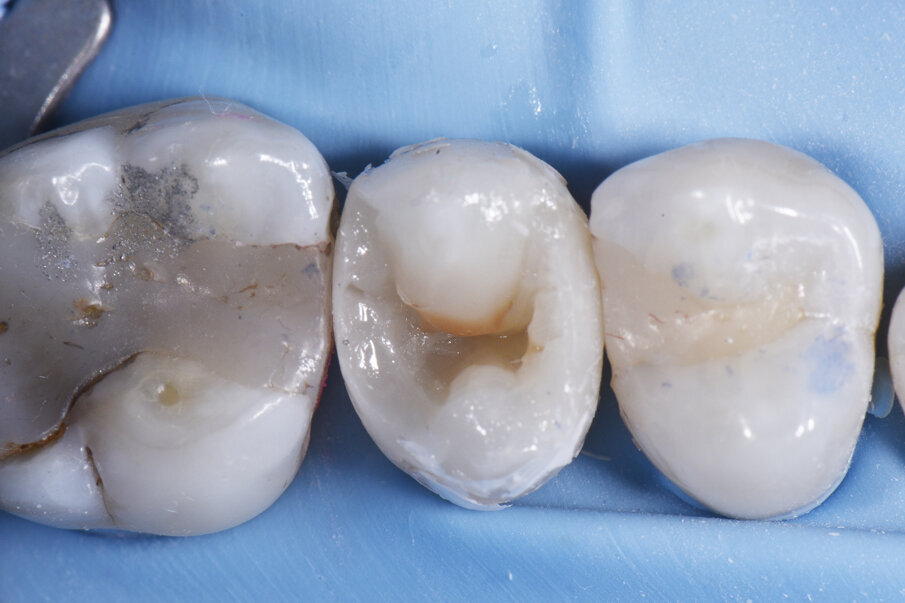

Marginal ridge formation using A2 ceram.x® SphereTEC™ one. Removal of sectional matrix assembly after this stage. Finish like a Class I restoration.

Buccal lobe placement using A2 ceram.x® SphereTEC™ one. Fissure stain placed in interlobar position.

Following the total etch bonding technique, Dentsply Sirona’s SDR® Plus was placed against the base of the proximal box floor as liner in very thin layers and cured, in an effort to ensure hybridisation and marginal integrity in this sensitive area before building the marginal ridge.